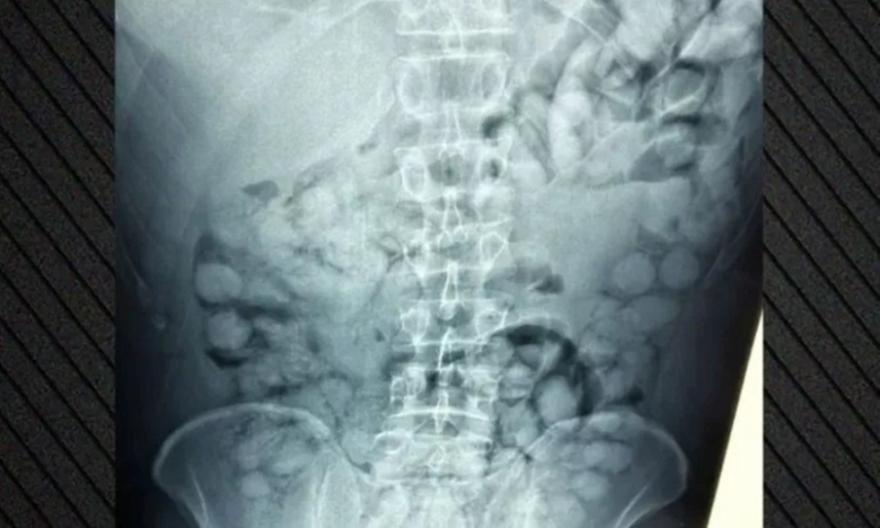

Όπως ανακοίνωσε η ΕΛ.ΑΣ., ο συλληφθείς είχε φτάσει στην Αθήνα μέσω Παρισιού και κατά τον έλεγχο διαπιστώθηκε ότι είχε καταπιεί περίπου 100 μικροδέματα της ναρκωτικής ουσίας.